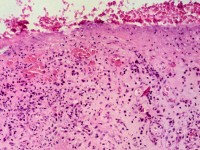

Histologie:

Pseudo-epitheliomateuze hyperplasie, tekenen van virale infectie zoals perinucleaire eosinofiele virusinsluitsels, vacuolaire veranderingen van het epitheel en

pycnotische kernen van keratinocyten. Lymfohistiocytair ontstekingsinfiltraat met plasmacellen.

Histologie van orf (ecthyma contagiosum) Histologie van orf (ecthyma contagiosum) Histologie van orf (ecthyma contagiosum)

histologie van orf histologie van orf histologie van orf